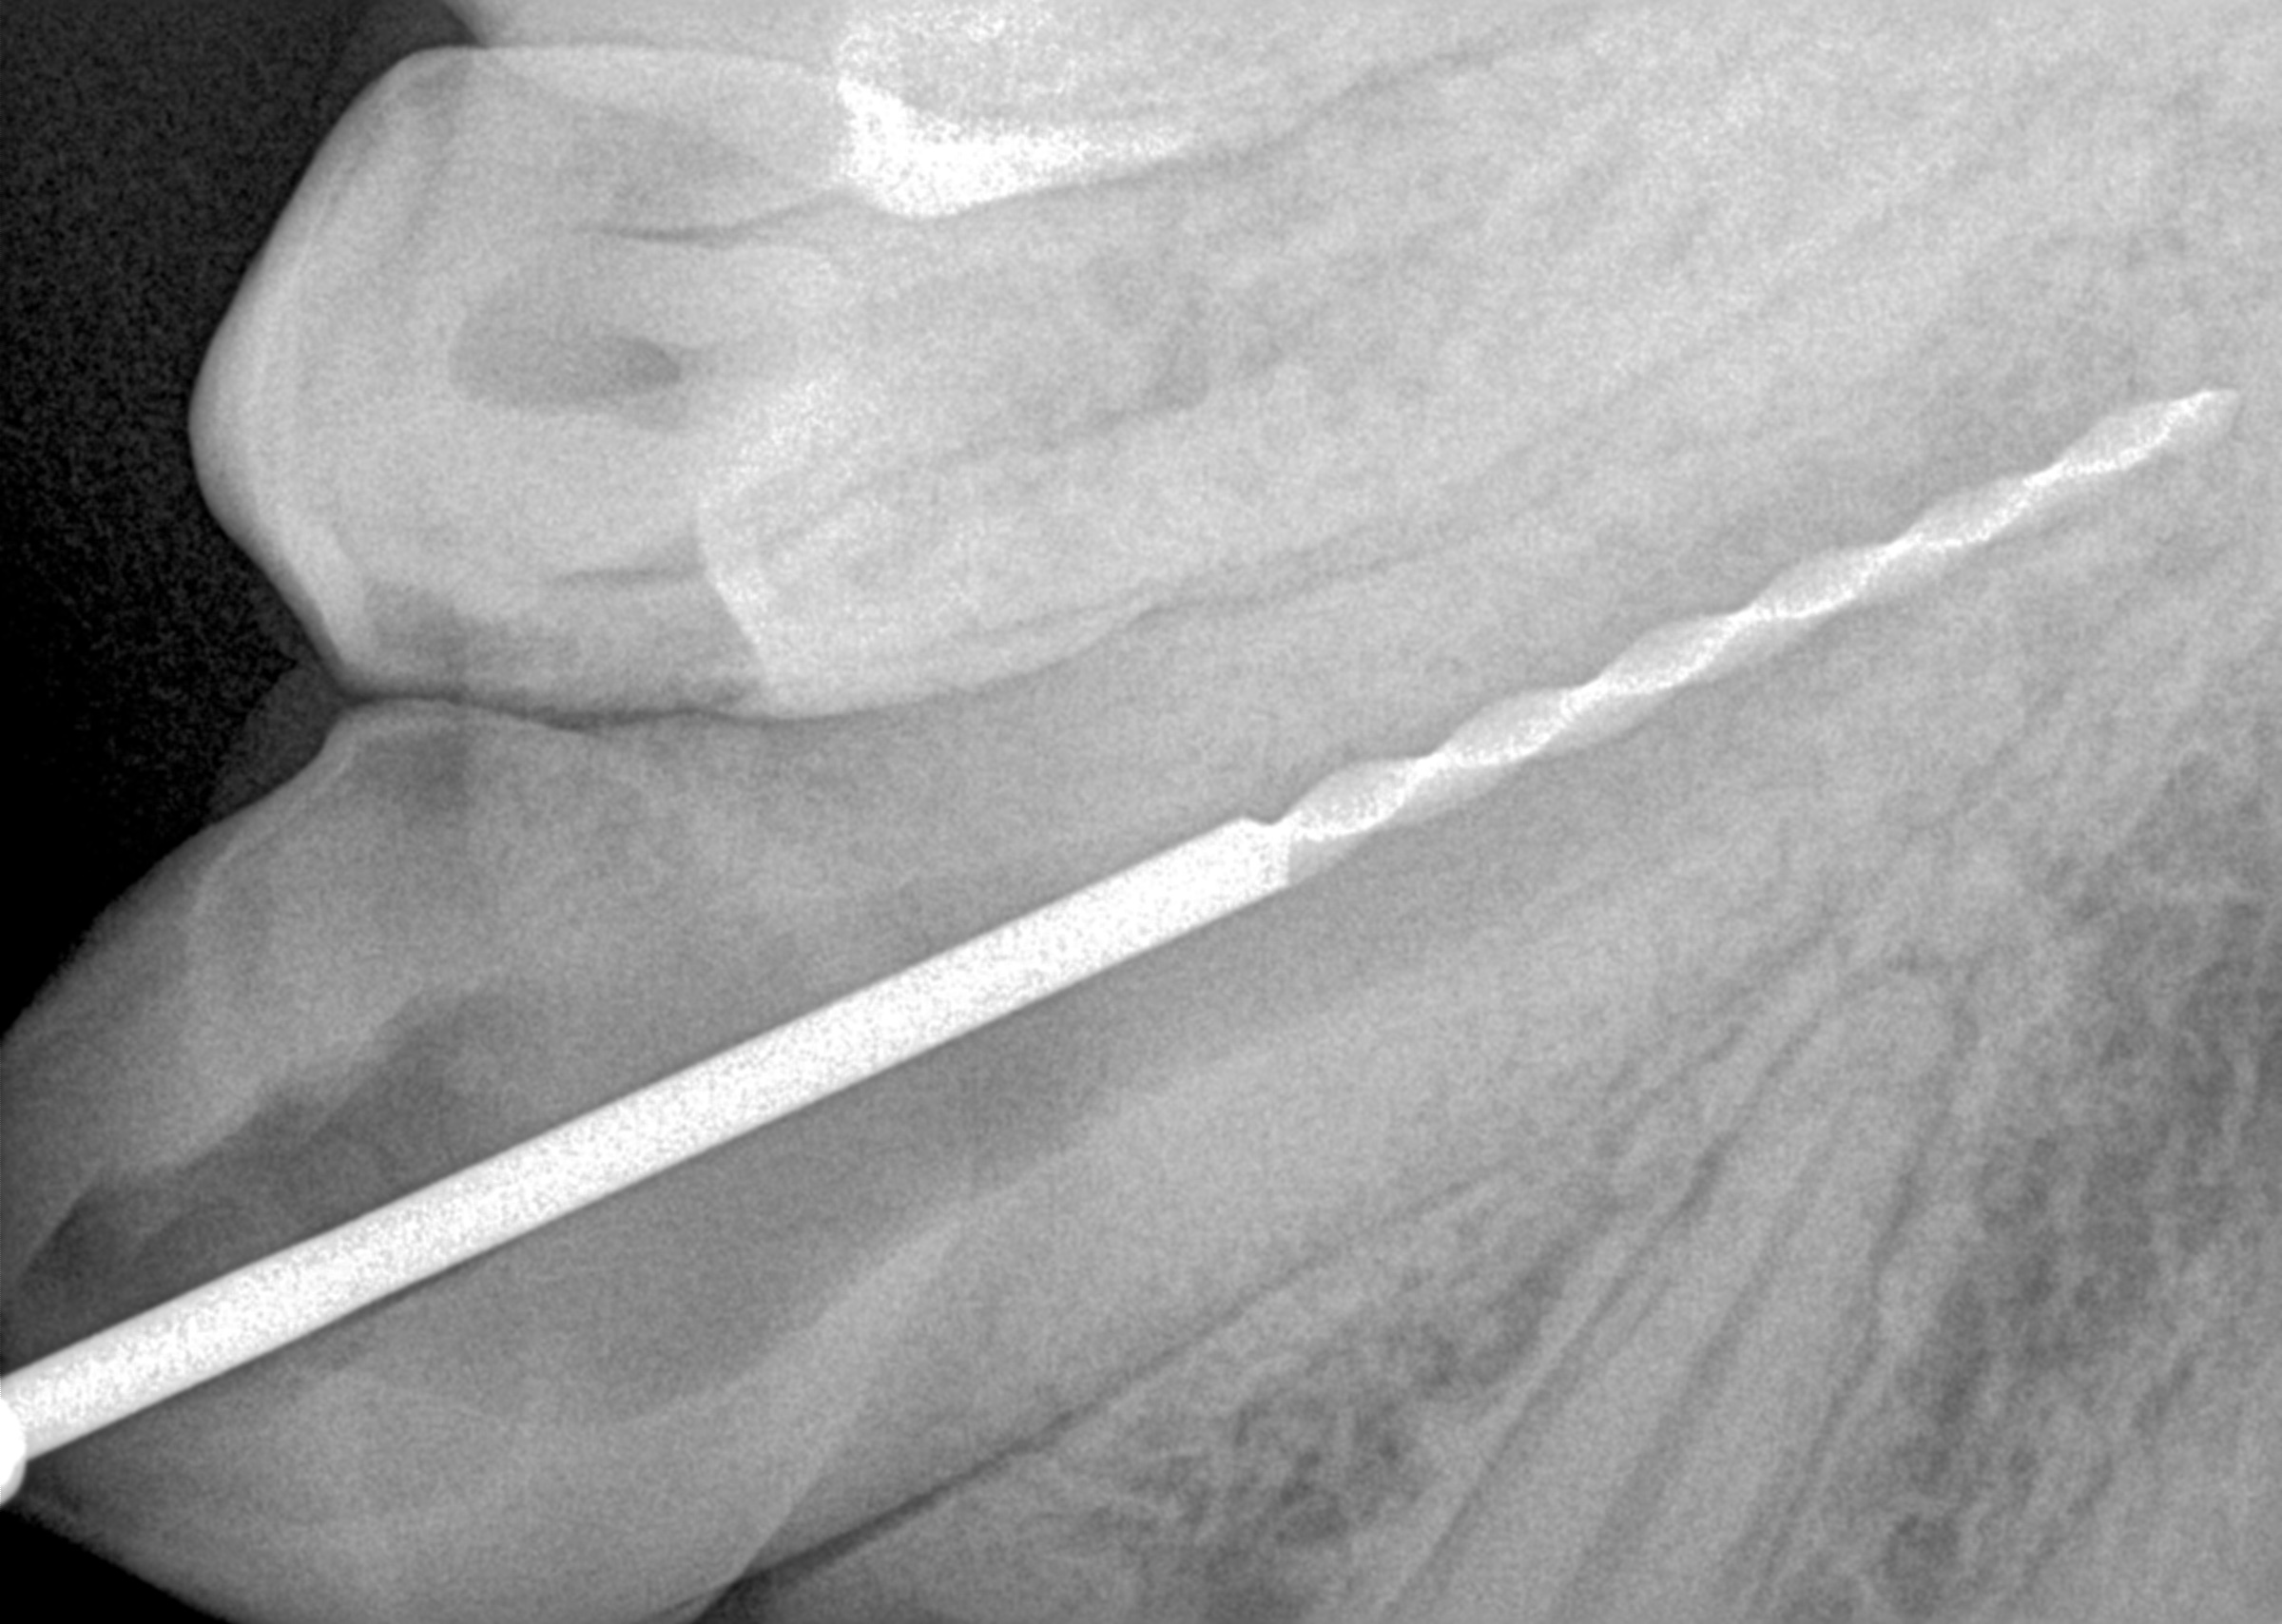

Radiograph of canine

Canine endo fill

Canine endo amalgam restoration

Exam: Fractured maxillary left canine (no. 15 or 207), extraoral chronic drainage tract adjacent to nostril and oral antral fistula where maxillary second molar had been extracted by veterinarian

Fractured canine with exposed pulp cavity